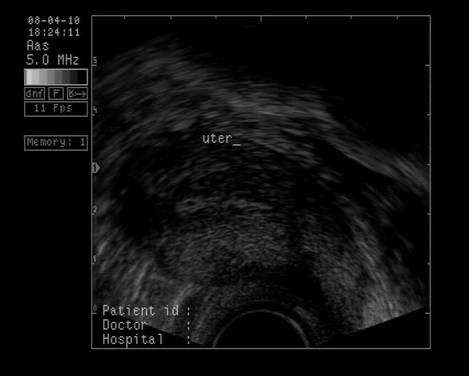

Uterul - situat intre vezica si rect, pozitia lui poate fi variabila, influentata si de umplerea vezici. De obicei, corpul uterin si colul au o relativa omogenitate interna ecografica. Cateodata imagini anecogene in peretele cervical reprezinta chiste Naboth.

Dimensiunile uterului la o pacienta nulipara matura, masurate transvaginal sunt de 7,3 cm x 4,0 cm x 3,2 cm. In general dimensiunile cresc cu paritatea si scad dupa menopauza.

Raportul intre corp si col este aproximativ de 1,6 in ceea ce priveste lungimea.[5,6]